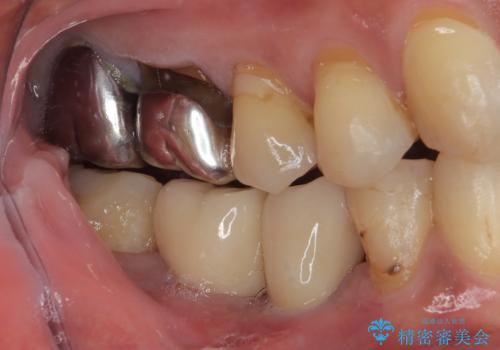

歯が割れて抜歯になってしまったとのことと、ブリッジの土台となる手前の歯は既に神経が取り除かれていて、こちらも破折するリスクが高いことから、咬合力に抵抗できるよう、インプラントによる補綴治療を行うこととしました。

手前の神経を取り除いている歯も、合わせて補綴治療を行うこととしました。

インプラント埋入時に植立具合の安定性を測定したところ、十分な数値が得られたため、速やかに仮歯を装着して咬合回復をさせることができました。

外科処置を1回に抑えることができ、あっという間に治療を終えることができました。